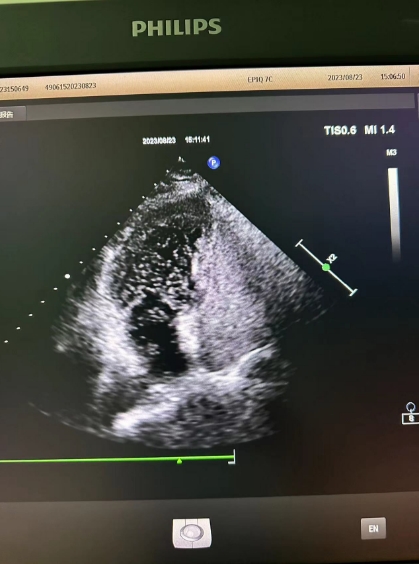

超聲心動(dòng)圖檢查發(fā)現(xiàn)可能存在卵圓孔未閉,經(jīng)心內(nèi)科會(huì)診,詳細(xì)詢問病情、仔細(xì)了解病史后,為進(jìn)一步明確診治,決定為患者進(jìn)行右心聲學(xué)造影檢查。右心聲學(xué)造影是一項(xiàng)無創(chuàng)、便捷的超聲檢查技術(shù),醫(yī)護(hù)人員首先在患者胳臂上建立一個(gè)靜脈通路,然后把含有微小氣泡的振蕩生理鹽水注入患者體內(nèi),同時(shí)將超聲探頭放在患者心前區(qū),借助超聲檢查設(shè)備,觀察進(jìn)入人體心腔的微小氣泡運(yùn)動(dòng)情況。

患者檢查后果然發(fā)現(xiàn)了異常,從屏幕上可以清晰看到,患者左心房內(nèi)很快出現(xiàn)了大量微小氣泡,這說明該患者的心臟存在著房水平由右向左的分流,提示有先天性卵圓孔未閉!根據(jù)這一檢查結(jié)果與患者及家屬溝通后,心內(nèi)科為其進(jìn)行了卵圓孔未閉封堵術(shù),最終改善了患者多年來的頭暈頭痛癥狀。